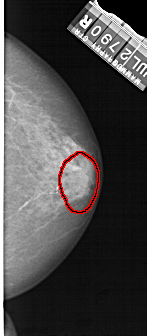

RIGHT_CC LINES 5026 PIXELS_PER_LINE 2191 BITS_PER_PIXEL 12 RESOLUTION 43.5 OVERLAY

FILE: A_1302_1.RIGHT_CC.OVERLAY

TOTAL_ABNORMALITIES 1

ABNORMALITY 1

LESION_TYPE CALCIFICATION TYPE PUNCTATE-AMORPHOUS DISTRIBUTION REGIONAL

ASSESSMENT 4

SUBTLETY 3

PATHOLOGY BENIGN

TOTAL_OUTLINES 1

BOUNDARY